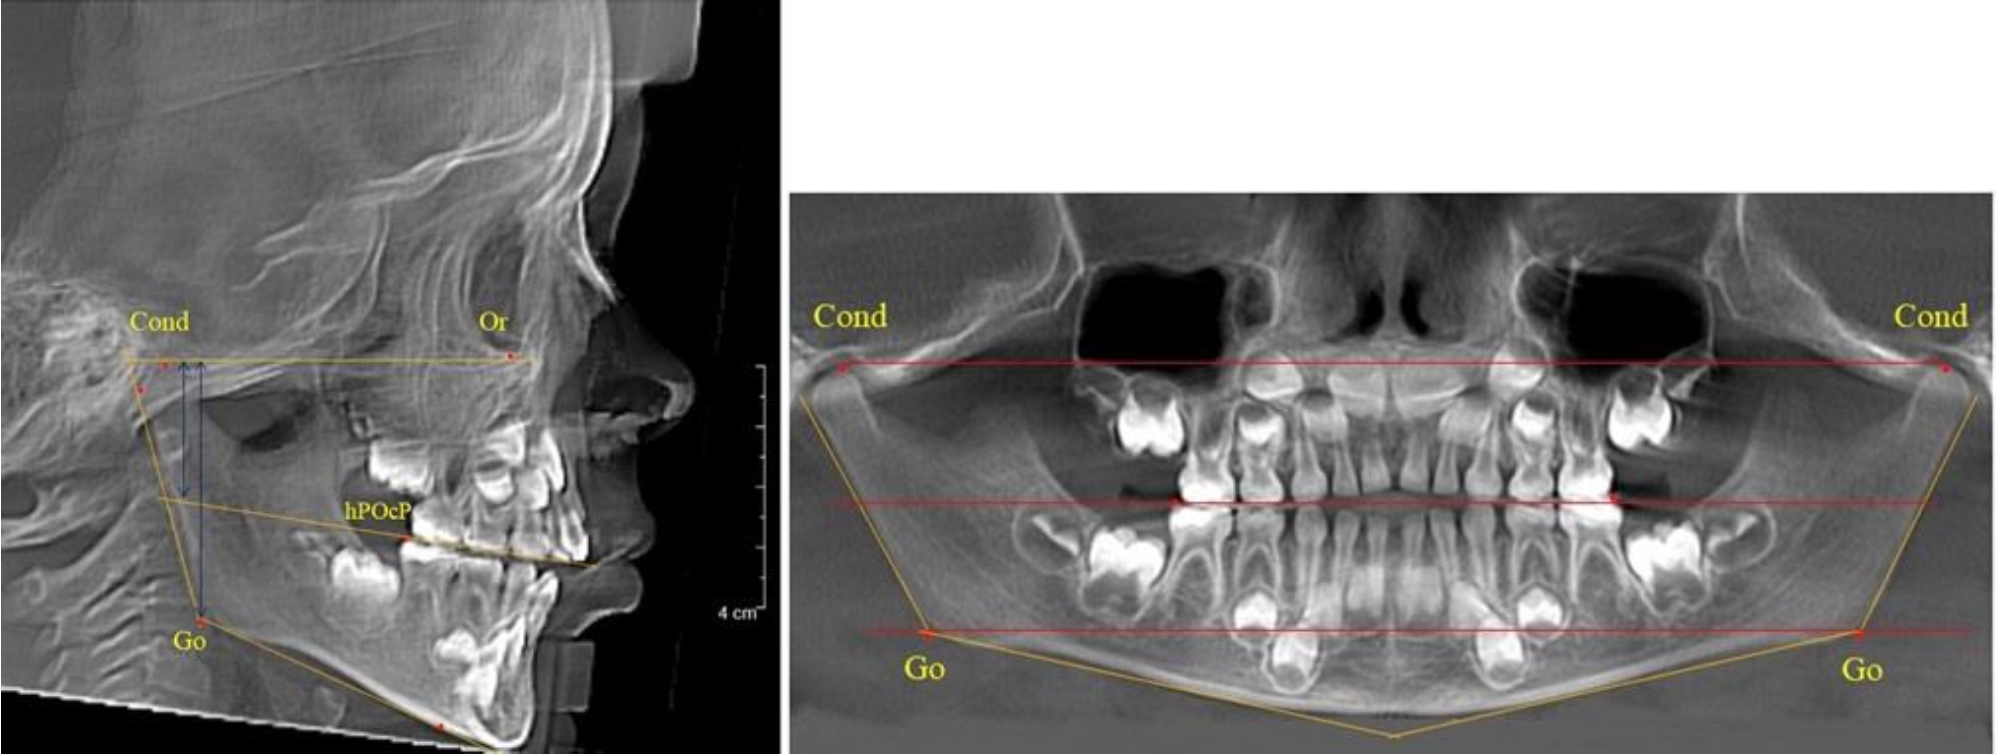

В 5-й группе были проанализированы 14 комплектов рентгенограмм, что составило (13,21 ± 3,29) % от общего числа. На всех рентгенограммах отмечен очередной этап подъема высоты прикуса, обусловленный прорезыванием вторых постоянных моляров. Окклюзионная линия делила ветвь на два отдела (рис. 5).

Рис. 5. ТРГ и ОПТГ пациента после смены молочных зубов и прорезывания вторых постоянных моляров

Высота ветви у детей 5-й группы составляла (62,87 ± 3,62) мм, что было достоверно больше, чем у детей других групп (р ˂ 0,05). При этом высота верхней окклюзионно-суставной части была (40,23 ± 2,01) мм, а нижней – (22,64 ± 1,78) мм. Высота верхней части была вдвое больше нижней, что и определяло особенности соразмерности частей ветви нижней челюсти в анализируемый возрастной период.

Относительные показатели соразмерности частей ветви нижней челюсти показали, что отношение высоты верхней части ветви к нижней в среднем составляло 1,78 ± 0,18. Отношение общей высоты ветви к верхней ее части составляло 1,56 ± 0,12, а отношение общей высоты ветви к нижней ее части было 2,78 ± 0,14, что и определяло особенности соразмерности частей ветви нижней челюсти в анализируемый возрастной период.

Таким образом, прорезывание постоянных зубов и смена молочных зубов постоянными изменяло не только высоту ветви нижней челюсти, но и изменяло соотношение ее частей, разделенных условной линией, являющейся продолжением окклюзионной линии рентгенограммы. Наиболее вариабельной структурой ветви являлась верхняя ее часть с суставным отростком. Окклюзионно-альвеолярная часть коррелировала с высотой зубочелюстных сегментов нижней челюсти.